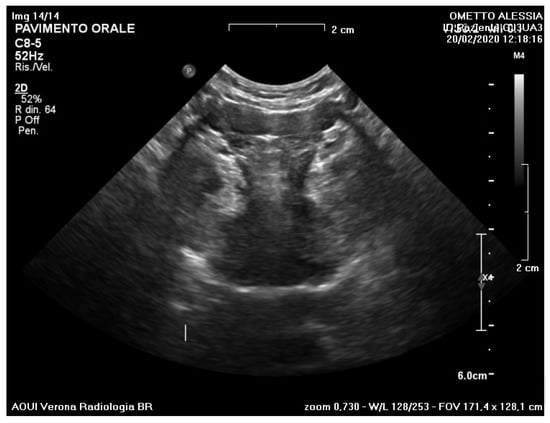

3. Results